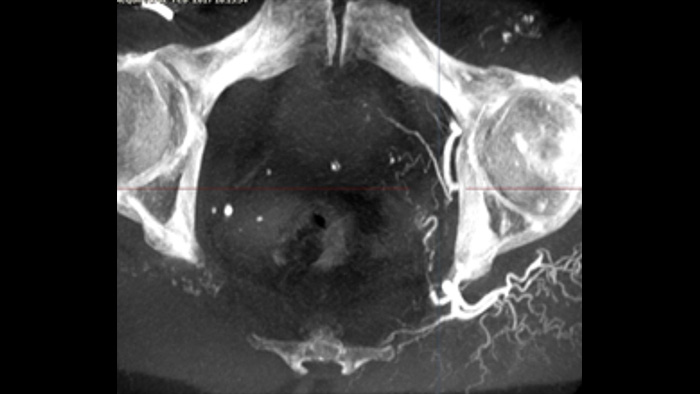

SmartCT Soft Tissue bietet eine Cone-Beam-CT-Erfassungstechnik (CBCT), die durch Schritt-für-Schritt-Anleitungen, erweiterte 3D-Darstellungs- und Messwerkzeuge, die alle auf dem Touchscreen-Modul am Tisch zugänglich sind, ergänzt wird. Damit Ihre CBCT-Bilder auf Anhieb gelingen und Ihr Arbeitsablauf effizient gelingt, werden Sie durch die wichtigsten Schritte geführt.